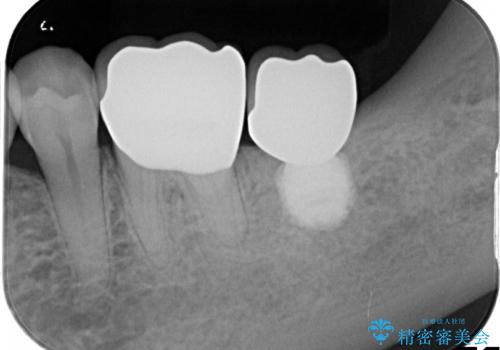

- 左下の1番後方の歯が欠損しており、インプラントにて咬合回復する計画としました。

レントゲン・CT撮影により骨の高さがあまりないことがわかり、ショートインプラントを選択しました。

また、清掃性を確保するために歯肉の移植も行うこととしました。